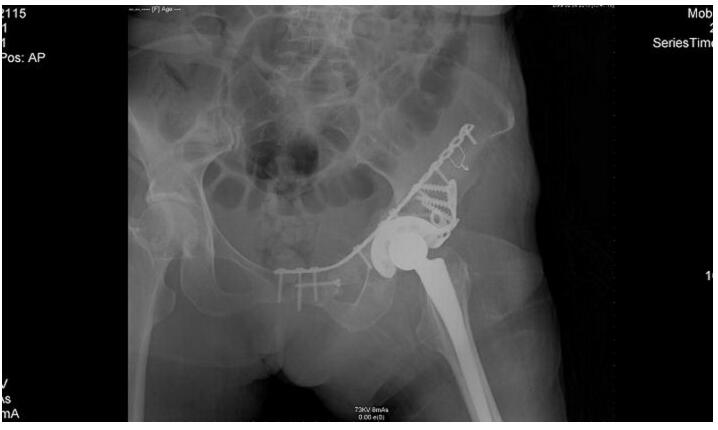

根据CT可见肿瘤累犯髋臼、耻骨下支、坐骨及部分髂骨,结合术前穿刺病理考虑软骨肉瘤,软骨肉瘤放化疗不敏感,手术为唯一根治性治疗手段,但耻骨上支后方闭孔动静脉与髂外或腹壁下动静脉会存在异常的吻合支,被称为“死亡之冠”,一旦不小心切断,很难实现止血,但是巨大的肿瘤往往遮挡手术的操作空间,很难有足够清晰的视野暴露血管,稍有不慎就将带来汹涌的出血并会危及生命。李涛主任带领整个团队经过术前反复讨论、缜密设计和充分准备,给病人实行了左骨盆肿瘤切除+全髋置换+髋臼修复+骨盆生物力学重建术,该术式利用自身骨质重建骨盆环,具有骨性愈合的特点,可以有效避免目前流行的单纯骨盆假体置换造成假体松动,脱位从而导致手术失败的缺点。

手术持续6个小时,术中出血3000ml,术后病人恢复良好,一周下地不负重拄拐行走,两周出院。